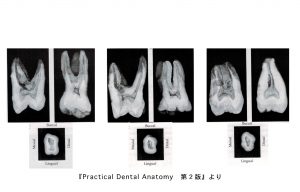

実際の下顎大臼歯の中身

これは下顎大臼歯を歯の神経に達するまでの穴をあけて真っ二つに割ったものです。根の先端にいくほどカーブしているのがわかりますね。

治療の実際

左の根の中にファイルという根の中を掃除する器具を入れています。器具をこのように入れていきます。この器具の先端は実は0.015mmという細さなのです。

写真は拡大してますのでそうは見えませんが、肉眼での治療はなかなか難しいのかなと思っていただけると幸いです。